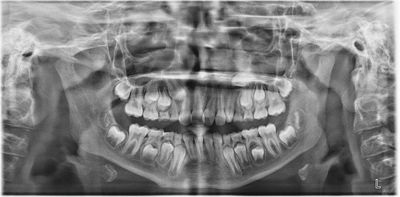

Still, one contributor reminded colleagues not to rule out nature entirely. They posted a case (Figs. 6–9) where an ectopic UL3, initially “the scariest” they’d seen, erupted spontaneously two years after the extraction of the primary canine, with no surgical or orthodontic intervention. “No voodoo,” they joked, “but plenty of hand-wringing.”

Fig. 6